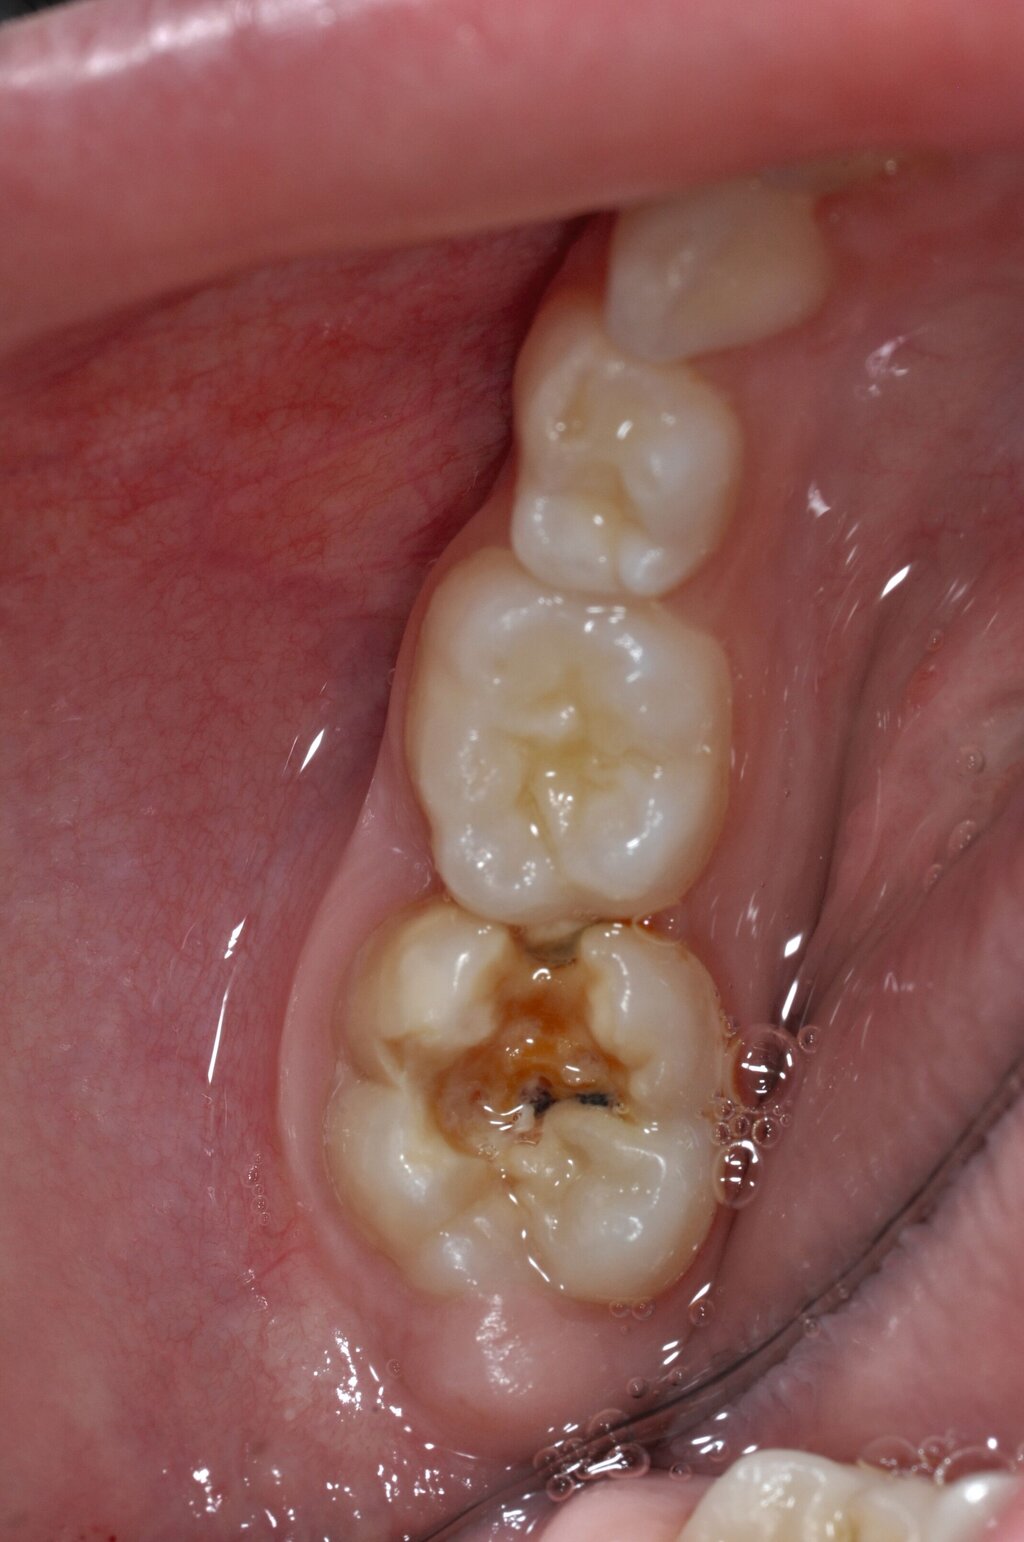

Diese Klassifikation dient als Grundlage für die Therapieempfehlungen. Deutlich wird, dass aufgrund der Symptomatik die Therapie der Zähne höchst unterschiedlich ausfällt. Dass etwa eine Opazität ohne Überempfindlichkeit (Index 1, Abbildung 1) ein anderes therapeutisches Vorgehen erfordert als ein Zahn mit nahezu komplettem Einbruch der Zahnoberfläche und mit Hypersensitivität (Index 4, Abbildung 2), ist offensichtlich.

Die Therapie C hat das Ziel, MIH-Zähne vorübergehend zu versorgen, bis der vollständige Durchbruch der Zähne eine adhäsive Restauration ermöglicht, um die hypersensiblen Zähne zu desensibilisieren oder/und die Mitarbeit für die weitere Behandlung aufzubauen. Vor dem Hintergrund des erhöhten Kariesrisikos dieser Zähne (Abbildung 2) muss durch die Maßnahmen eine Kariesprogression vermieden werden.

Der Vorteil der Methode ist, dass die betroffenen Zähne auch ohne Lokalanästhesie und Präparation versorgt werden können. Die temporäre Versorgung ermöglicht es, die Patienten an die zahnärztliche Behandlung zu gewöhnen. Häufig führt diese temporäre Versorgung auch zu einer Reduktion der Hypersensitivität der MIH-Zähne. Nachteil der GIZ-Versorgung ist das Risiko einer Füllungsfraktur oder eines vollständigen Verlusts der Füllung (Abbildung 4). Aktuelle Erhebungen bestätigen eine Erfolgsrate von über 80 Prozent nach einem bis zwei Jahren [Durmus et al., 2021; Mahfouz et al., 2025].

Der Behandlungsfall (Abbildung 4d) veranschaulicht die Schwächen des Verfahrens. Wird das Angebot der regelmäßigen Kontrollen nicht wahrgenommen, so droht bei Verlust der Füllung die Kariesprogression. In dem vorliegenden Fall konnte jedoch eine endodontische Maßnahme vermieden und durch die selektive Kariesentfernung die Zahnhartsubstanz weitestgehend erhalten werden.